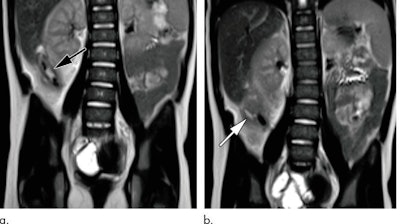

As the primary diagnostic imaging modality, MRI visualized the appendix in 349 (87%) of the 402 patients. A diagnosis for the remaining 53 patients (13%) was provided based on secondary signs of appendicitis, such as the detection of fluid or an elevated T2-weighted signal in the expected region of the appendix. Overall, MRI achieved sensitivity of 98%, specificity of 99%, and accuracy of 99%. Among the 304 patients with negative findings for appendicitis, MRI provided an alternate diagnosis for 113 (37%).